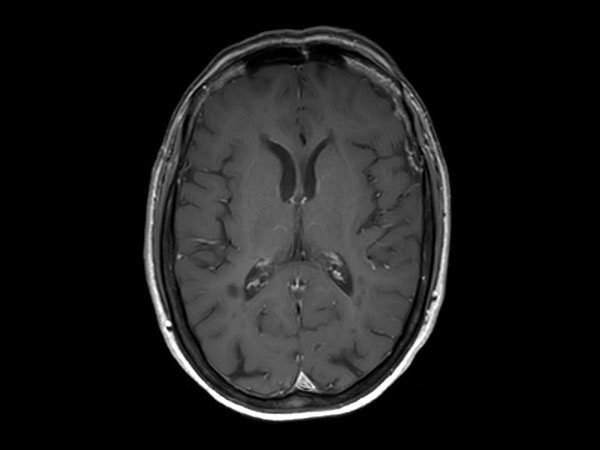

3D T1w FFE Compressed SENSE

3D T1w FFE (reformat) Compressed SENSE